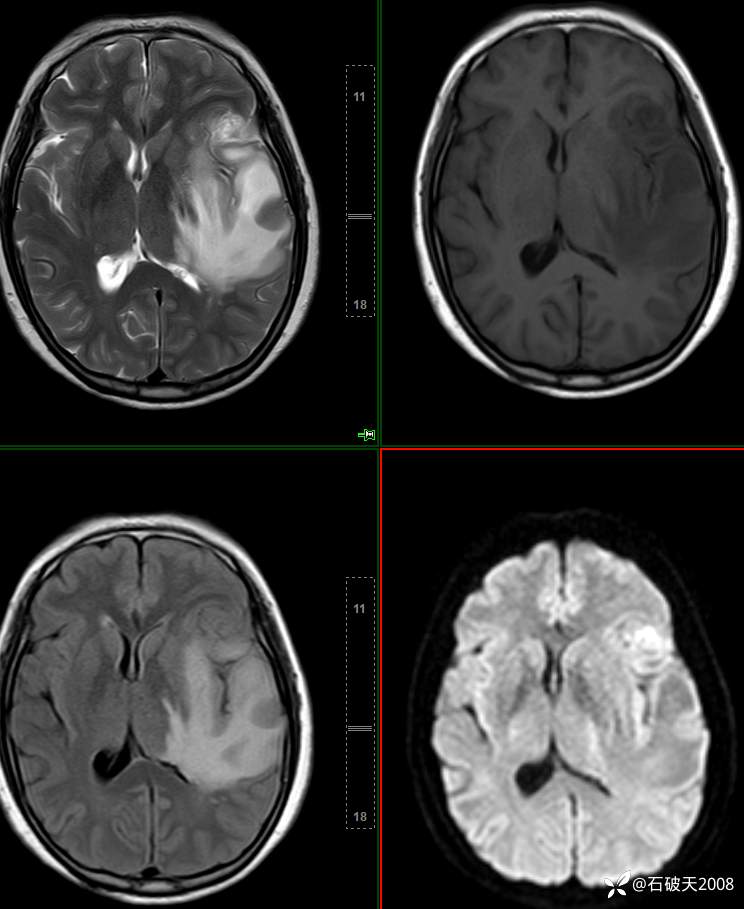

平扫